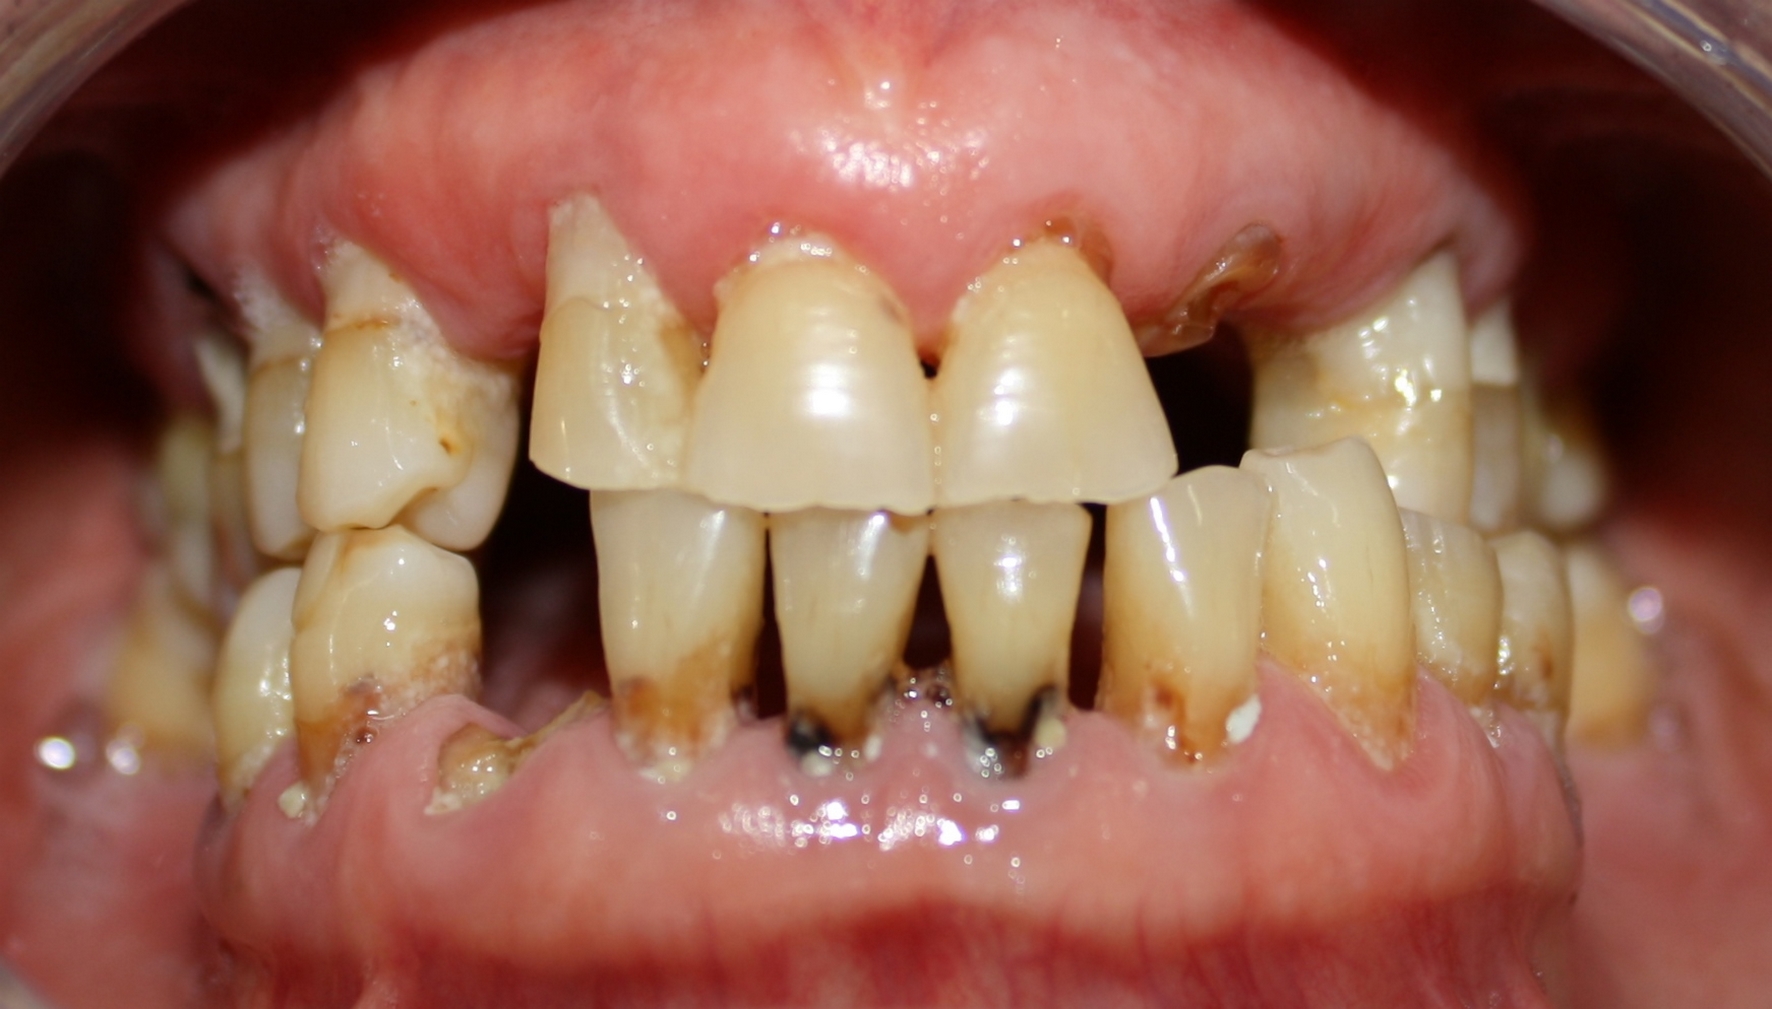

Osteoradionecrosis (ORN) is one of the most severe oral complications after the head and neck cancer treatment. Tooth extraction, through its traumatic stimulation, is identified as an important predisposing factor. Indications and preventive methods for carrying out these procedures in irradiated patients are questioned, thus, establishing appropriate protocols is essential. This article reports a case of multiple tooth extractions in a cancer patient whose preventive measures were taken without the occurrence of complications. Based on a literature review, this paper accounts the appropriate indications of this procedure, the risk of developing osteoradionecrosis, and the prevention possibilities for this sequela. In addition, this report addresses a viable oral rehabilitation alternative after this kind of surgery by using overdenture on the lower jaw teeth.